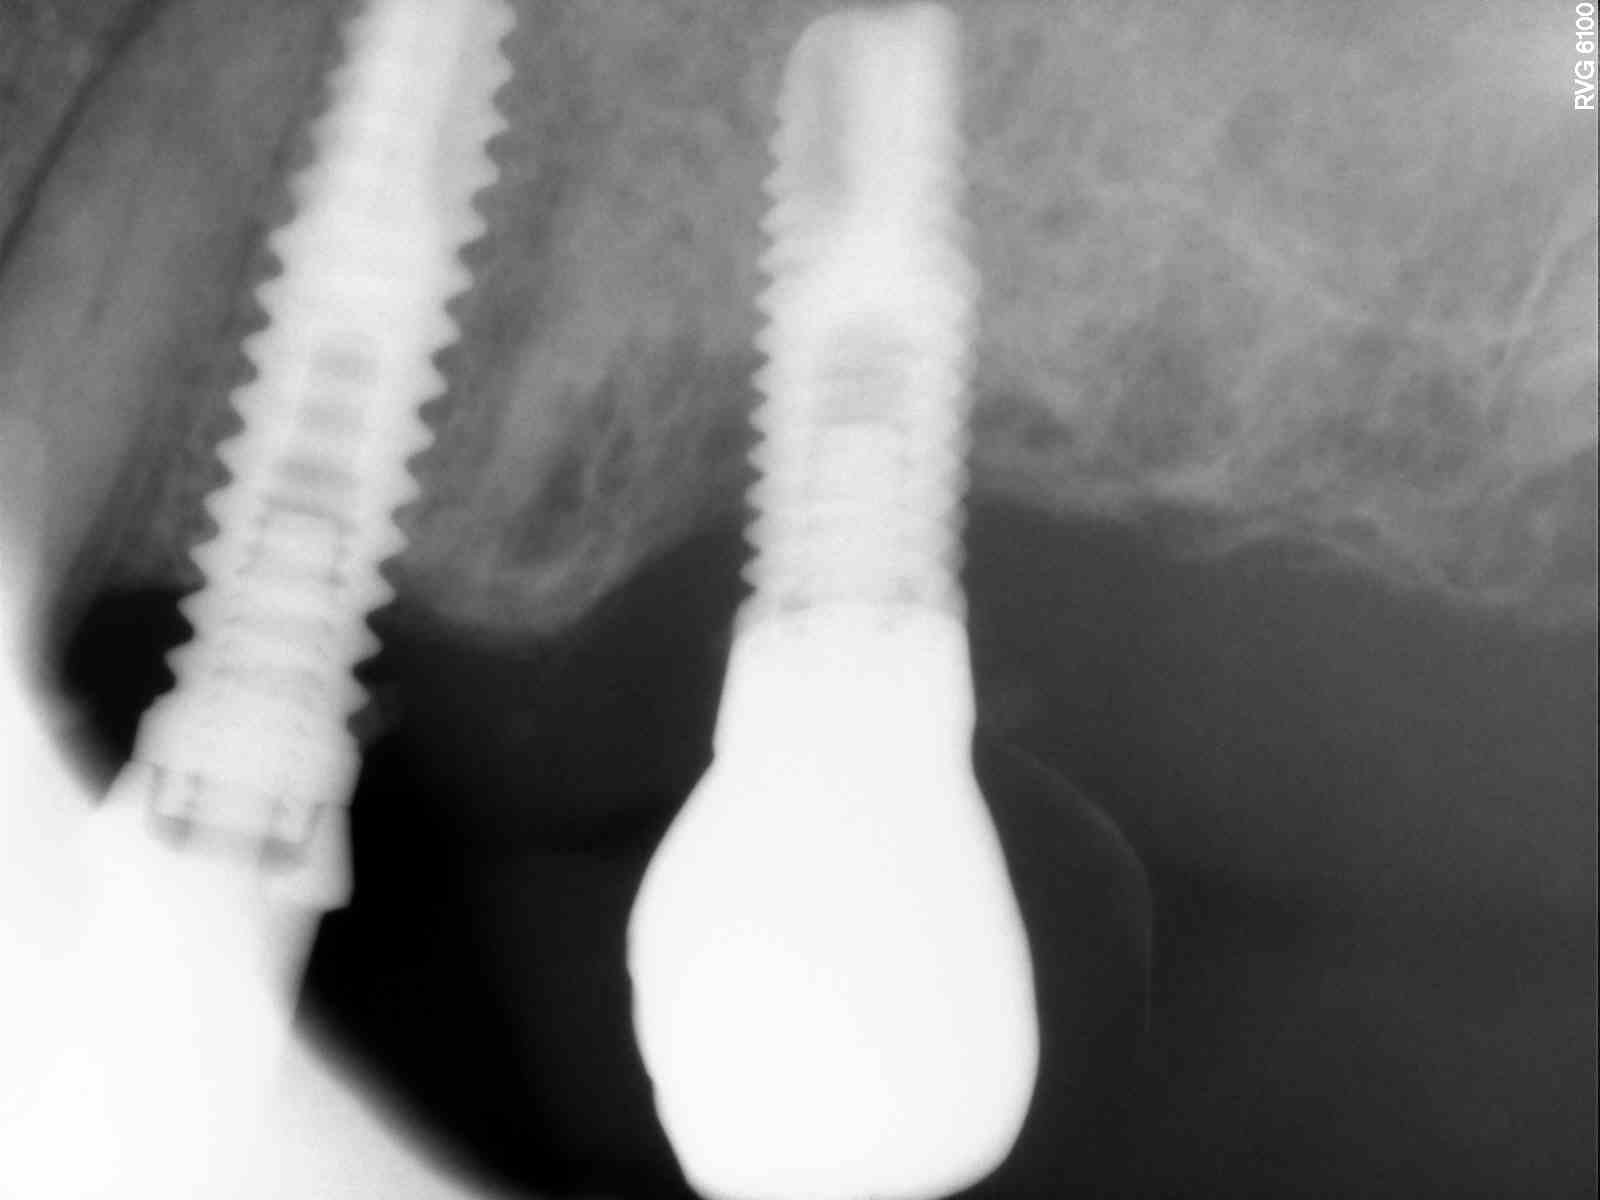

Buenas tardes, agradecería que me identificaran estos implantes. Los pilares además parecen diferentes. Es una paciente con sobredentadura con una antiguedad de 18 años que se hizo en Colombia. Muchas [...]